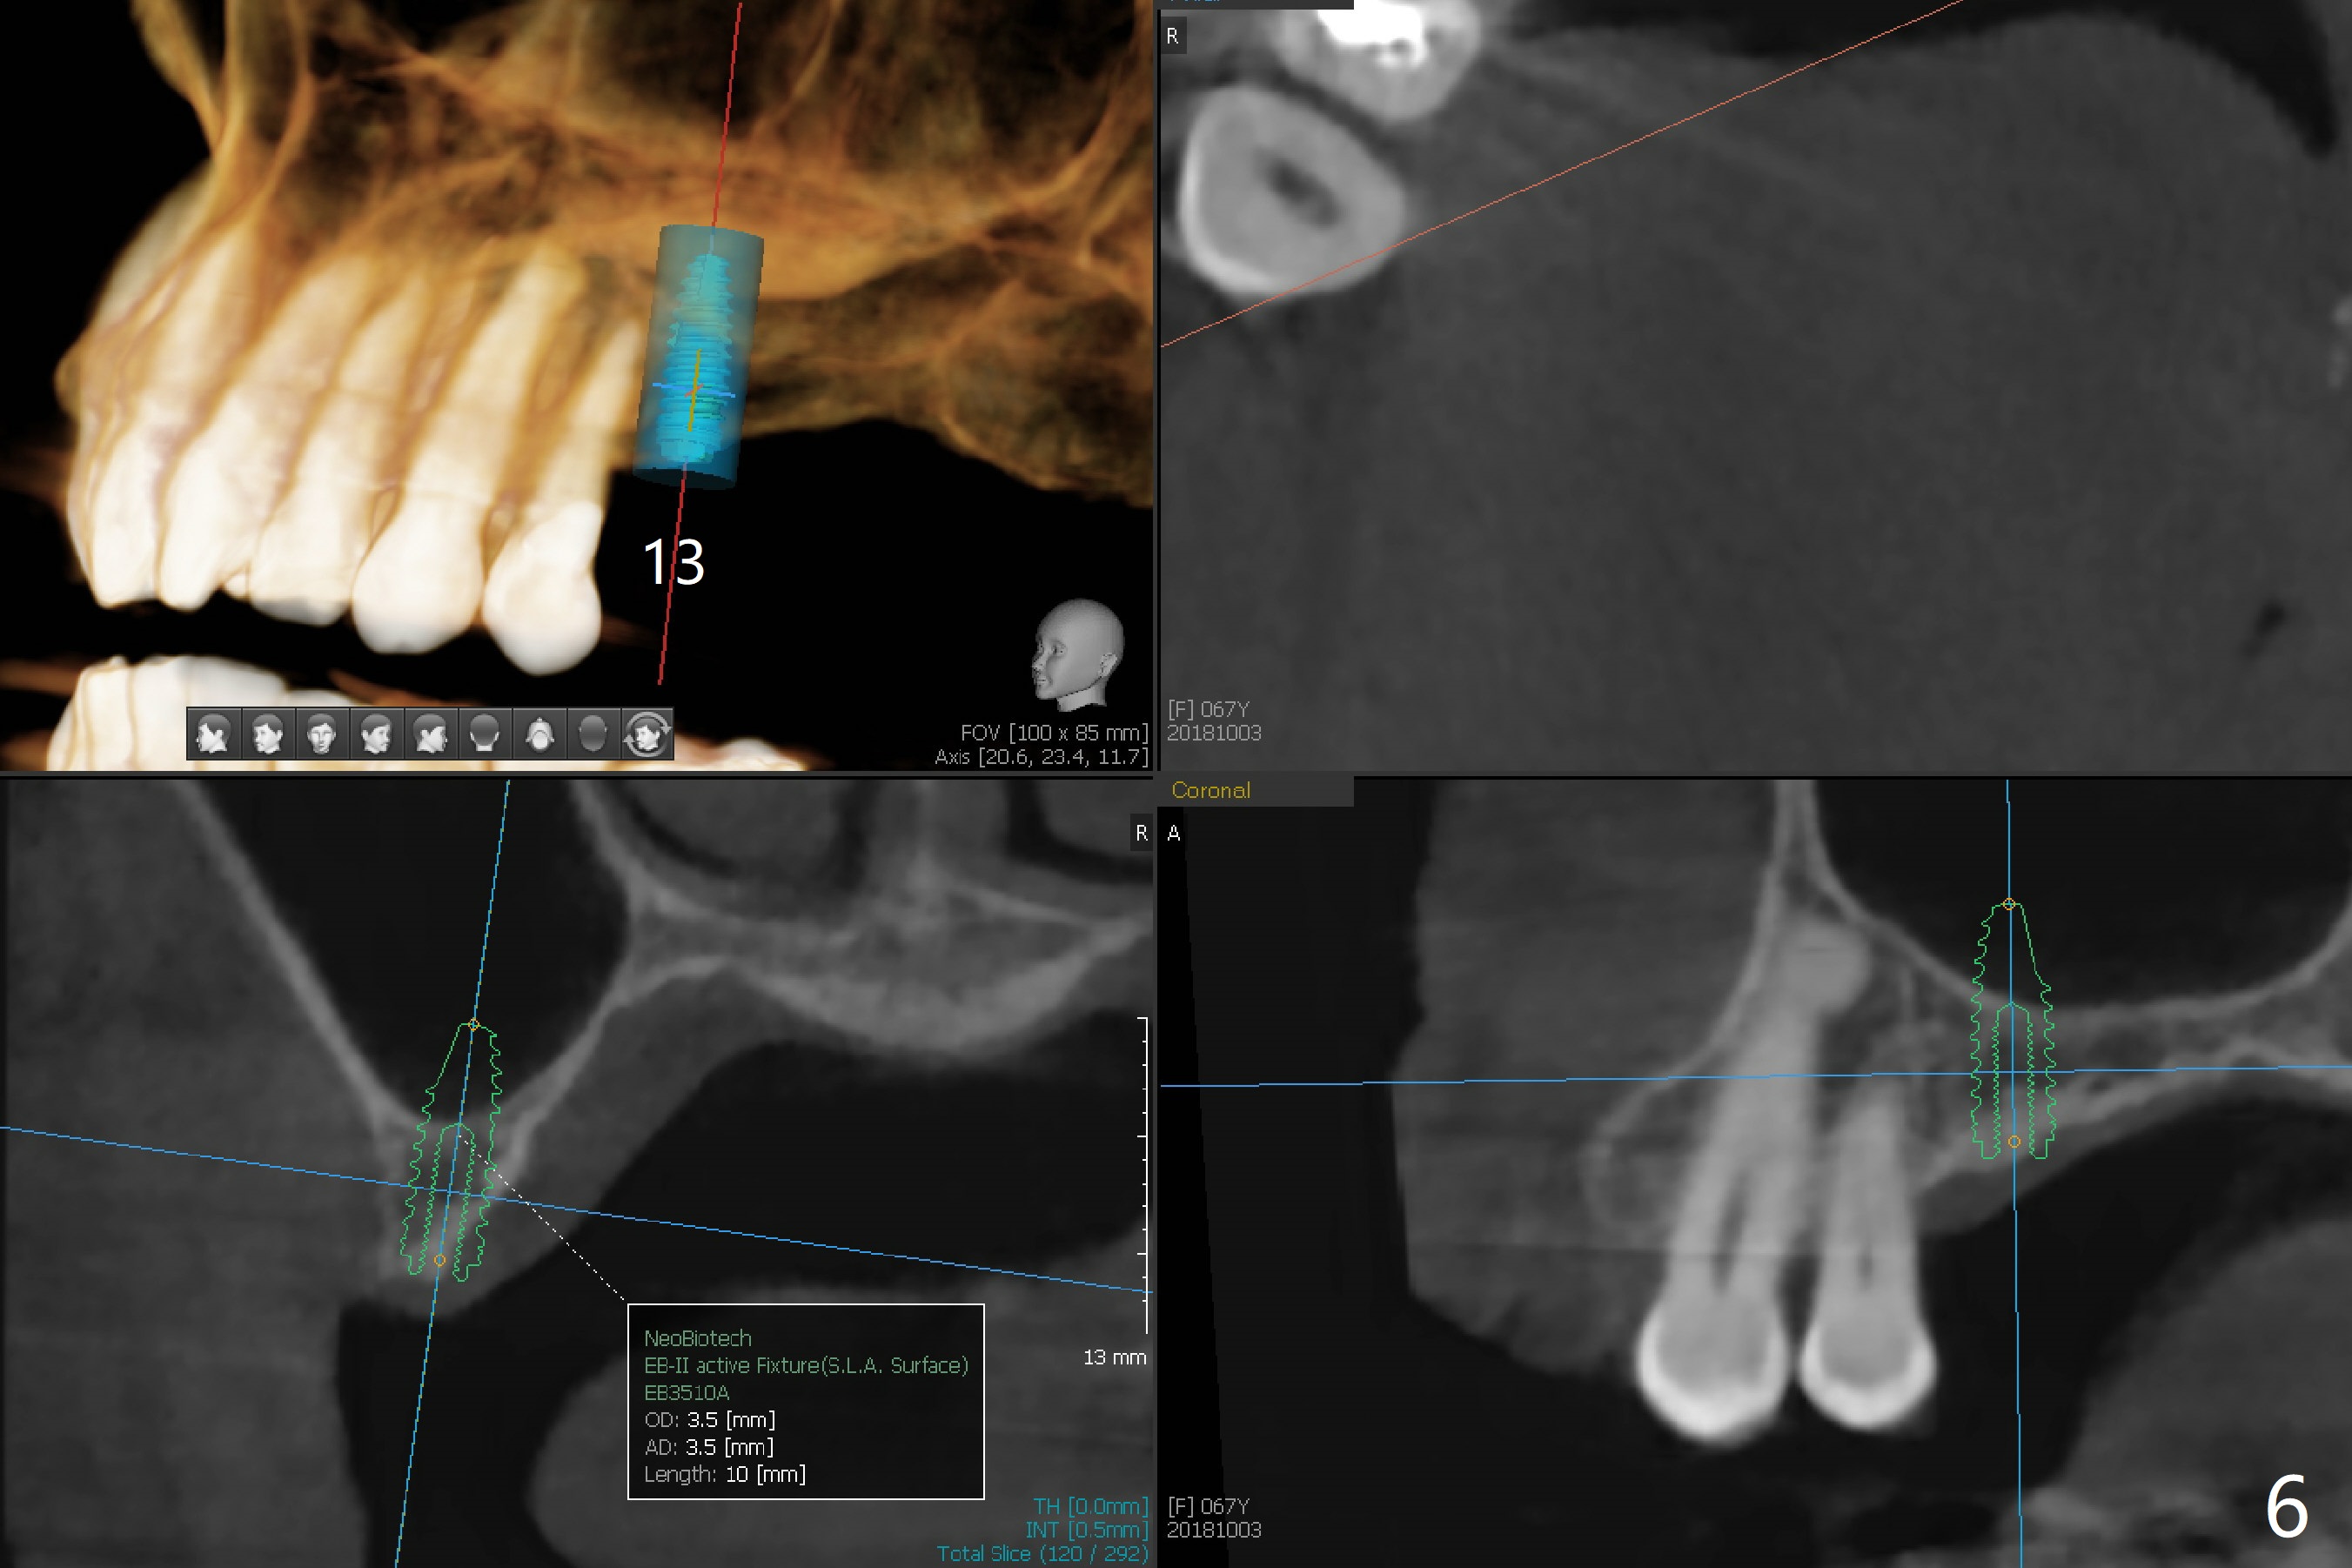

A 67-year-old woman masticates on the right side (Fig.1 (5 years post #30 RCT), as compared to Fig.4,6). One year and 6 months later, there is a fistula mesiobuccal to the tooth #30 (Fig.2 >,4) with mesial root fracture (Fig.3 >). Impression is taken for guide; a 5x11.5 mm implant will be placed slightly distal and lingual to the center of the septum (Fig.5).